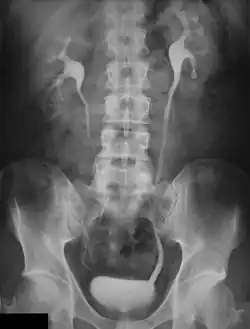

An intravenous pyelogram (IVP), also called an intravenous urogram (IVU), is a radiological procedure used to visualize abnormalities of the urinary system, including the kidneys, ureters, and bladder. Unlike a kidneys, ureters, and bladder x-ray (KUB), which is a plain (that is, noncontrast) radiograph, an IVP uses contrast to highlight the urinary tract.

In IVP, the contrast agent is given through a vein (intravenously), allowed to be cleared by the kidneys and excreted through the urinary tract as part of the urine.[5] If this is contraindicated for some reason, a retrograde pyelogram, with the contrast flowing upstream, can be done instead.